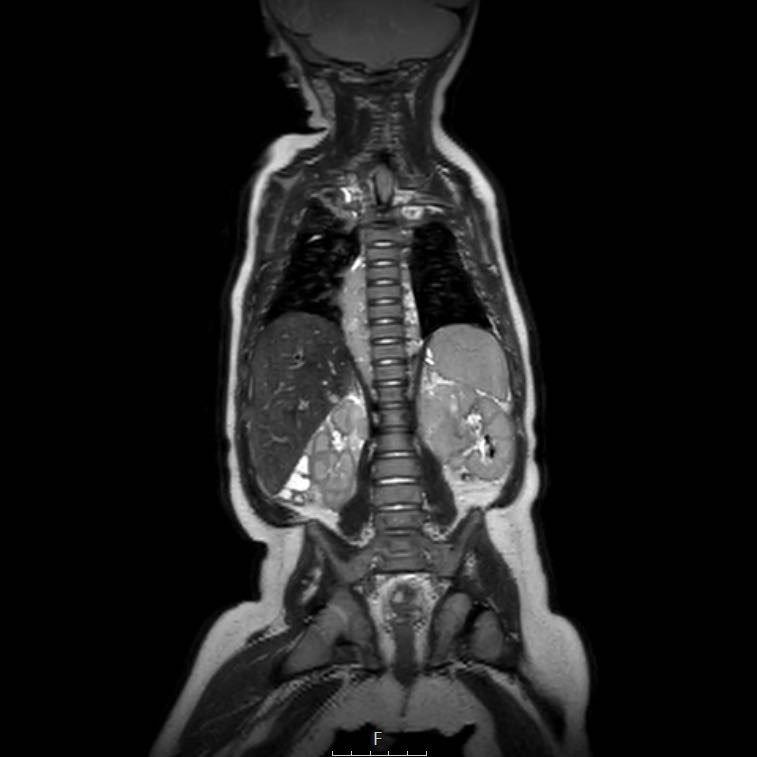

Cuộn qua chuỗi ảnh T2 theo mặt phẳng coronal.

Nghiên cứu các hình ảnh và sau đó tiếp tục đọc.

The findings are:

- Mass with encasement of the aorta and splanchnic vessels.

- Lan rộng dọc theo cột sống ngực nhưng không xâm lấn vào ống sống.

- Small liver metastases.

- Left supraclavicular mass.